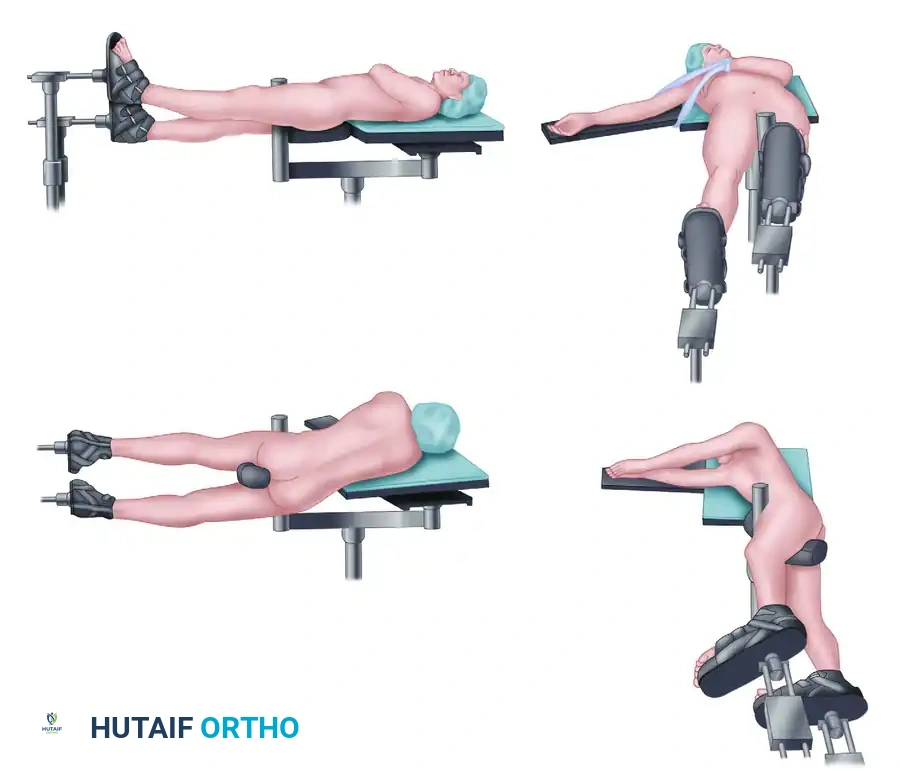

Retrograde femoral nailing can be defined as any femoral nailing technique with a distal entry from the condyles or through an intercondylar, intra-articular starting point. For this chapter,retrograde femoral nailing will refer to nails with an intercondylar starting point that extend through the shaft region to the proximal femur. In certain fracture situations, shortened nails (supracondylar nails) can be used with the same starting point for fixation of distal femoral fractures. ## ANATOMY The femoral shaft is tubular in shape over the extent of the isthmus, gradually flaring infraisthmally into the distal femur, which is trapezoidal in cross-section. The entry point for the retrograde femoral nail is located at the distal end of the patellofemoral grove, just anterior to the posterior cruciate ligament insertion ( FIG 1A). Radiographically, this is located in the midline or just medial to the midline between the condyles on the anteroposterior (AP) view and laterally just anterior to the line of Blumensaat as it meets the trochlear grove ( FIG 1B,C).5, 12, 14, 15, 18 This flat articular area has minimal to no contact with the patella until 120 degrees of flexion. 1, 5  ---

---  ### FIG 1 • A. Distal femur viewed end on, with ideal starting point for retrograde femoral nailing identified (asterisk) just anterior to the posterior cruciate ligament insertion. B,C. AP and lateral radiographs of the knee, with the initial starting guidewire positioned at the ideal starting point for retrograde femoral nailing. The radiographic landmark for the trochlear groove (TG) is indicated on the AP radiograph and for the line of Blumensaat (BL) on the lateral radiograph. Pertinent proximal anatomy includes neurovascular structures anterior to the proximal femur, close to interlocking screw insertion sites. 24 The femoral artery is medial to the proximal femur, with branches that cross the anterior femur more than 4 cm distal to the lesser trochanter. Branches of the femoral nerve cross more proximal starting 4 cm distal to the piriformis fossa. Damage to neurovascular structures caused by proximal locking screw insertion can be avoided or minimized by avoiding medial dissection and with placement at or above the lesser trochanter ( FIG 2). ## PATHOGENESIS Femoral shaft fractures are markers of high-energy injuries. 10, 12, 13, 14, 23, 27 Studies have shown that 38% of trauma patients diagnosed with a femoral shaft fracture have additional injuries. 3, 7, 8, 26 In femur fracture patients with associated injuries, the most common findings are other musculoskeletal injuries (93%), thoracic injuries (62%), head injuries (59%), abdominal injuries (35%), and facial injuries (16%). 7

### FIG 1 • A. Distal femur viewed end on, with ideal starting point for retrograde femoral nailing identified (asterisk) just anterior to the posterior cruciate ligament insertion. B,C. AP and lateral radiographs of the knee, with the initial starting guidewire positioned at the ideal starting point for retrograde femoral nailing. The radiographic landmark for the trochlear groove (TG) is indicated on the AP radiograph and for the line of Blumensaat (BL) on the lateral radiograph. Pertinent proximal anatomy includes neurovascular structures anterior to the proximal femur, close to interlocking screw insertion sites. 24 The femoral artery is medial to the proximal femur, with branches that cross the anterior femur more than 4 cm distal to the lesser trochanter. Branches of the femoral nerve cross more proximal starting 4 cm distal to the piriformis fossa. Damage to neurovascular structures caused by proximal locking screw insertion can be avoided or minimized by avoiding medial dissection and with placement at or above the lesser trochanter ( FIG 2). ## PATHOGENESIS Femoral shaft fractures are markers of high-energy injuries. 10, 12, 13, 14, 23, 27 Studies have shown that 38% of trauma patients diagnosed with a femoral shaft fracture have additional injuries. 3, 7, 8, 26 In femur fracture patients with associated injuries, the most common findings are other musculoskeletal injuries (93%), thoracic injuries (62%), head injuries (59%), abdominal injuries (35%), and facial injuries (16%). 7  ---